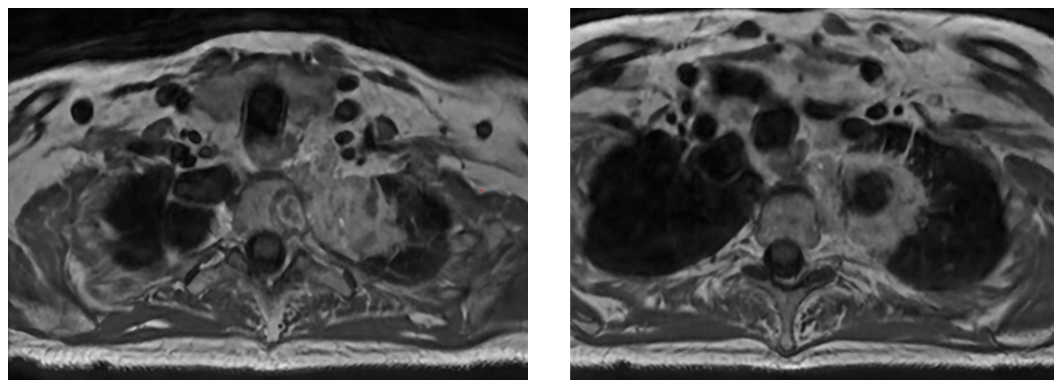

- MRI confirmed vertebral body invasion.

MRI Scan

There are several potential approaches to this case. Given that the mass extends into the vertebral body and the T2 neural foramen, with unclear borders, the International Spine Radiosurgery Consortium consensus guidelines were utilized, with inclusion of the ipsilateral neural foramen and vertebral body substructures. Choices A and C are too limited with respect to vertebral body coverage, and actually appear to miss gross disease. A thin-slice MRI scan was used for treatment planning and a spinal cord PRV was utilized to ensure appropriate coverage with adequate sparing of the spinal cord.